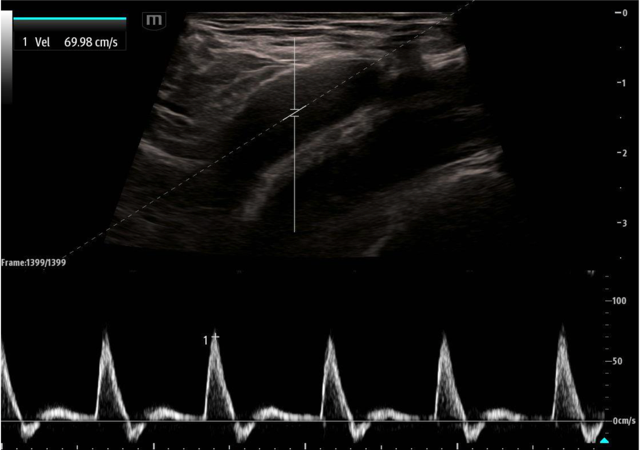

While the use of compression and color doppler aim to provide a qualitative assessment of pulsatile flow, pulsed wave doppler (PWD) of the large arteries can provide both qualitative and quantitative assessment of blood flow. Using the PWD mode, a sampling gate is centered within the artery in long axis and flow is measured. Most research thus far has focused on the peak systolic velocity (PSV) and end diastolic velocity (EDV), with more limited study of mean diastolic velocity (MDV).

The proof of concept was first published in 2015 by Adedipe et al who showed doppler measurements of carotid blood flow during cardiac arrest was feasible.11 Measurements were obtained by trained emergency physicians and investigators were able to complete a scanning protocol that included both color doppler and pulsed wave doppler measurements (PSV, EDV, MDV). Cohen et al. followed this in 2022 and showed pulsed wave doppler of the femoral artery was more accurate than manual palpation at either the femoral or carotid artery (95.3% vs. 54.0%; p < 0.001) across 213 pulse checks in 54 patients.12 A secondary outcome of that same study showed that a PSV ≥ 20 cm/s accurately detected an arterial line pulse SBP ≥ 60 mmHg with an accuracy of 91.4% and area under the receiver operating curve = 0.975. Lastly, in 2023, Haddad et al. showed the diagnostic accuracy of this same PSV cut off (≥ 20 cm/sec) for detecting ROSC with SBP of 60 mmHg was 89% (95% CI: 82%-94%) versus 59% (95% CI: 49%-68%) and 58% (95% CI: 48%-67%) for ETCO2 20 and 25 mmHg.13

May2025Sonographic Fig 3 psv pulse check.pngImage 3. Pulsed wave doppler of the femoral artery in long axis showing a PSV of approximately 70 cm/sec.